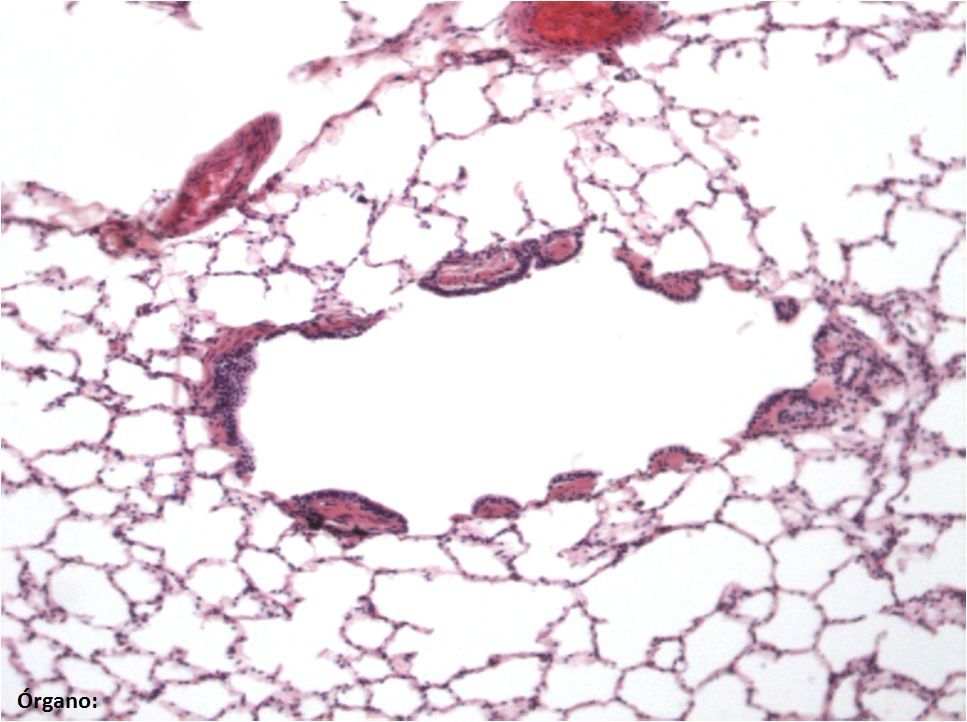

Escriba el nombre de las estructuras marcadas y del órgano (abajo a la izquierda) especificando si es de ave o mamífero (ej. molleja de ave). Nota: tenga en cuenta los acentos y las faltas de ortografía.

Answer

• Pulmón de mamífero

• Bronquiolo respiratorio

• Saco alveolar

• Conducto alveolar